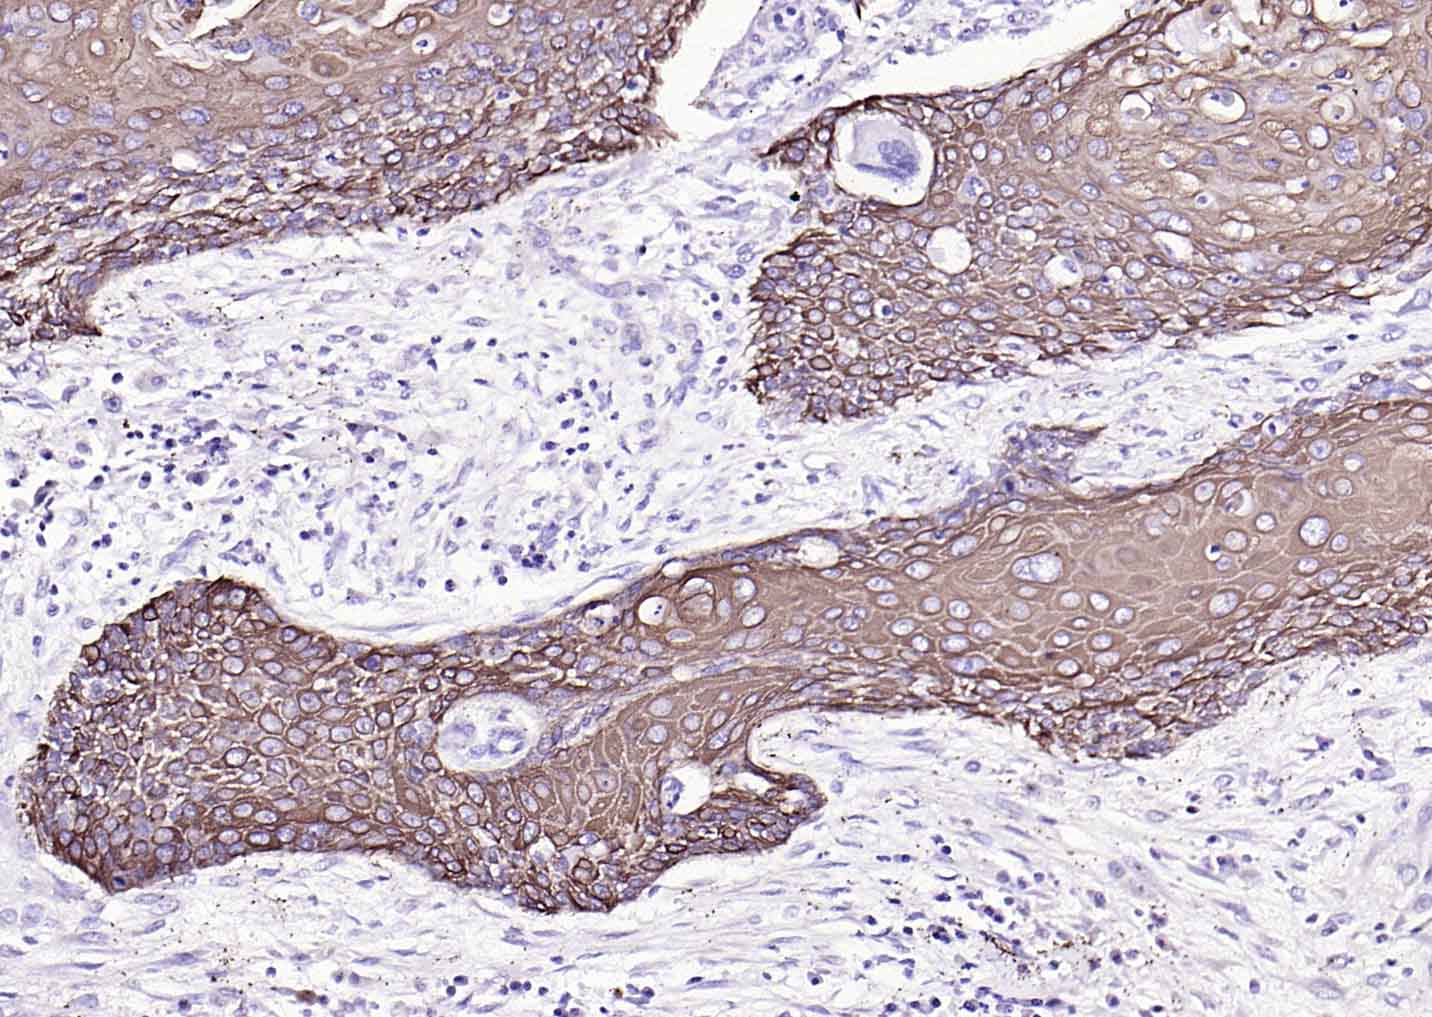

IHC-PHuman1:100-500

细胞角蛋白17单克隆抗体-bsm-33087M细胞角蛋白17单克隆抗体-bsm-33087M细胞角蛋白17单克隆抗体-bsm-33087M细胞角蛋白17单克隆抗体-bsm-33087M细胞角蛋白17单克隆抗体-bsm-33087M细胞角蛋白17单克隆抗体-bsm-33087M细胞角蛋白17单克隆抗体-bsm-33087M细胞角蛋白17单克隆抗体-bsm-33087M细胞角蛋白17单克隆抗体-bsm-33087M细胞角蛋白17单克隆抗体-bsm-33087M细胞角蛋白17单克隆抗体-bsm-33087M细胞角蛋白17单克隆抗体-bsm-33087M